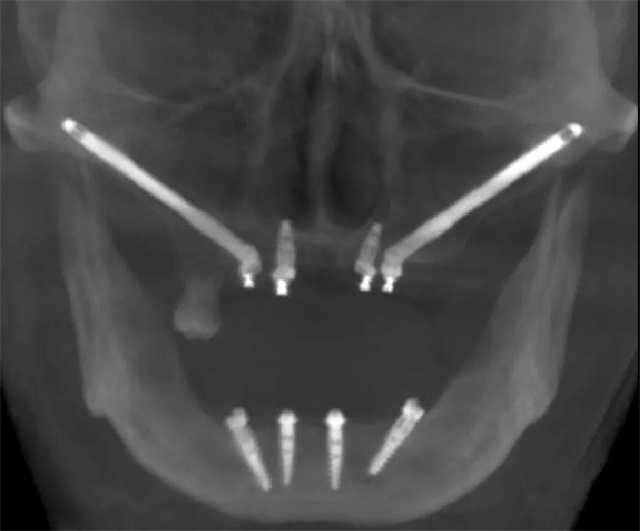

企鹅医生·正夫口腔熊靖宇院长作为国内著名的疑难复杂种植牙专家,受邀出席第二十五届华南国际口腔展览会,并在“华南展卡瓦大讲堂—诺保科种植专场”发表了主题为《穿颧穿翼技术在疑难种植中的应用》精彩演讲,现场汇集了口腔行业名师名家,一同为口腔同仁们带来创新的思维、前沿的技术理念以及实用的临床经验,为口腔界带来一场行业的学术盛宴。

面对上颌骨骨量严重不足的情况下,颧骨种植成上颌骨严重萎缩患者种牙新选择。他介绍,多颗牙或全口牙种植与建设桥梁相似,桥墩越稳越牢固,桥墩的位置要选在承受力强的地方才可靠。牙弓就像一个弧形的桥,在满足修复为前提的条件下,面部的任何有骨的部位都可以作为“桥墩”基地来考虑种植,对于上颌骨极端骨缺失的患者,想要术后即刻修复,可以考虑把植体往前外上方放在面部的颧骨上,往后放在上颌骨后面的蝶骨翼板上,这些地方都是面部非常结实的“桥墩”,把萎缩牙槽骨需要的支撑力量引到面部这些有良好骨质的部位,有点类似生活中斜拉桥,有效避开没有骨质的上颌窦区,这样萎缩的牙槽骨就有希望即刻种植、即刻修复。经过最近几年大量的穿翼种植,熊靖宇院长逐渐发现了规律,即“熊氏三角规律”。

最后熊靖宇院长进行了总结,严重萎缩的上颌骨可以选择穿颧种植和穿翼板种植,能达到即刻负重的结果,从而消除了骨移植的依赖,极大的改善患者对固定咬合的需求,拓展了口腔种植的范畴。